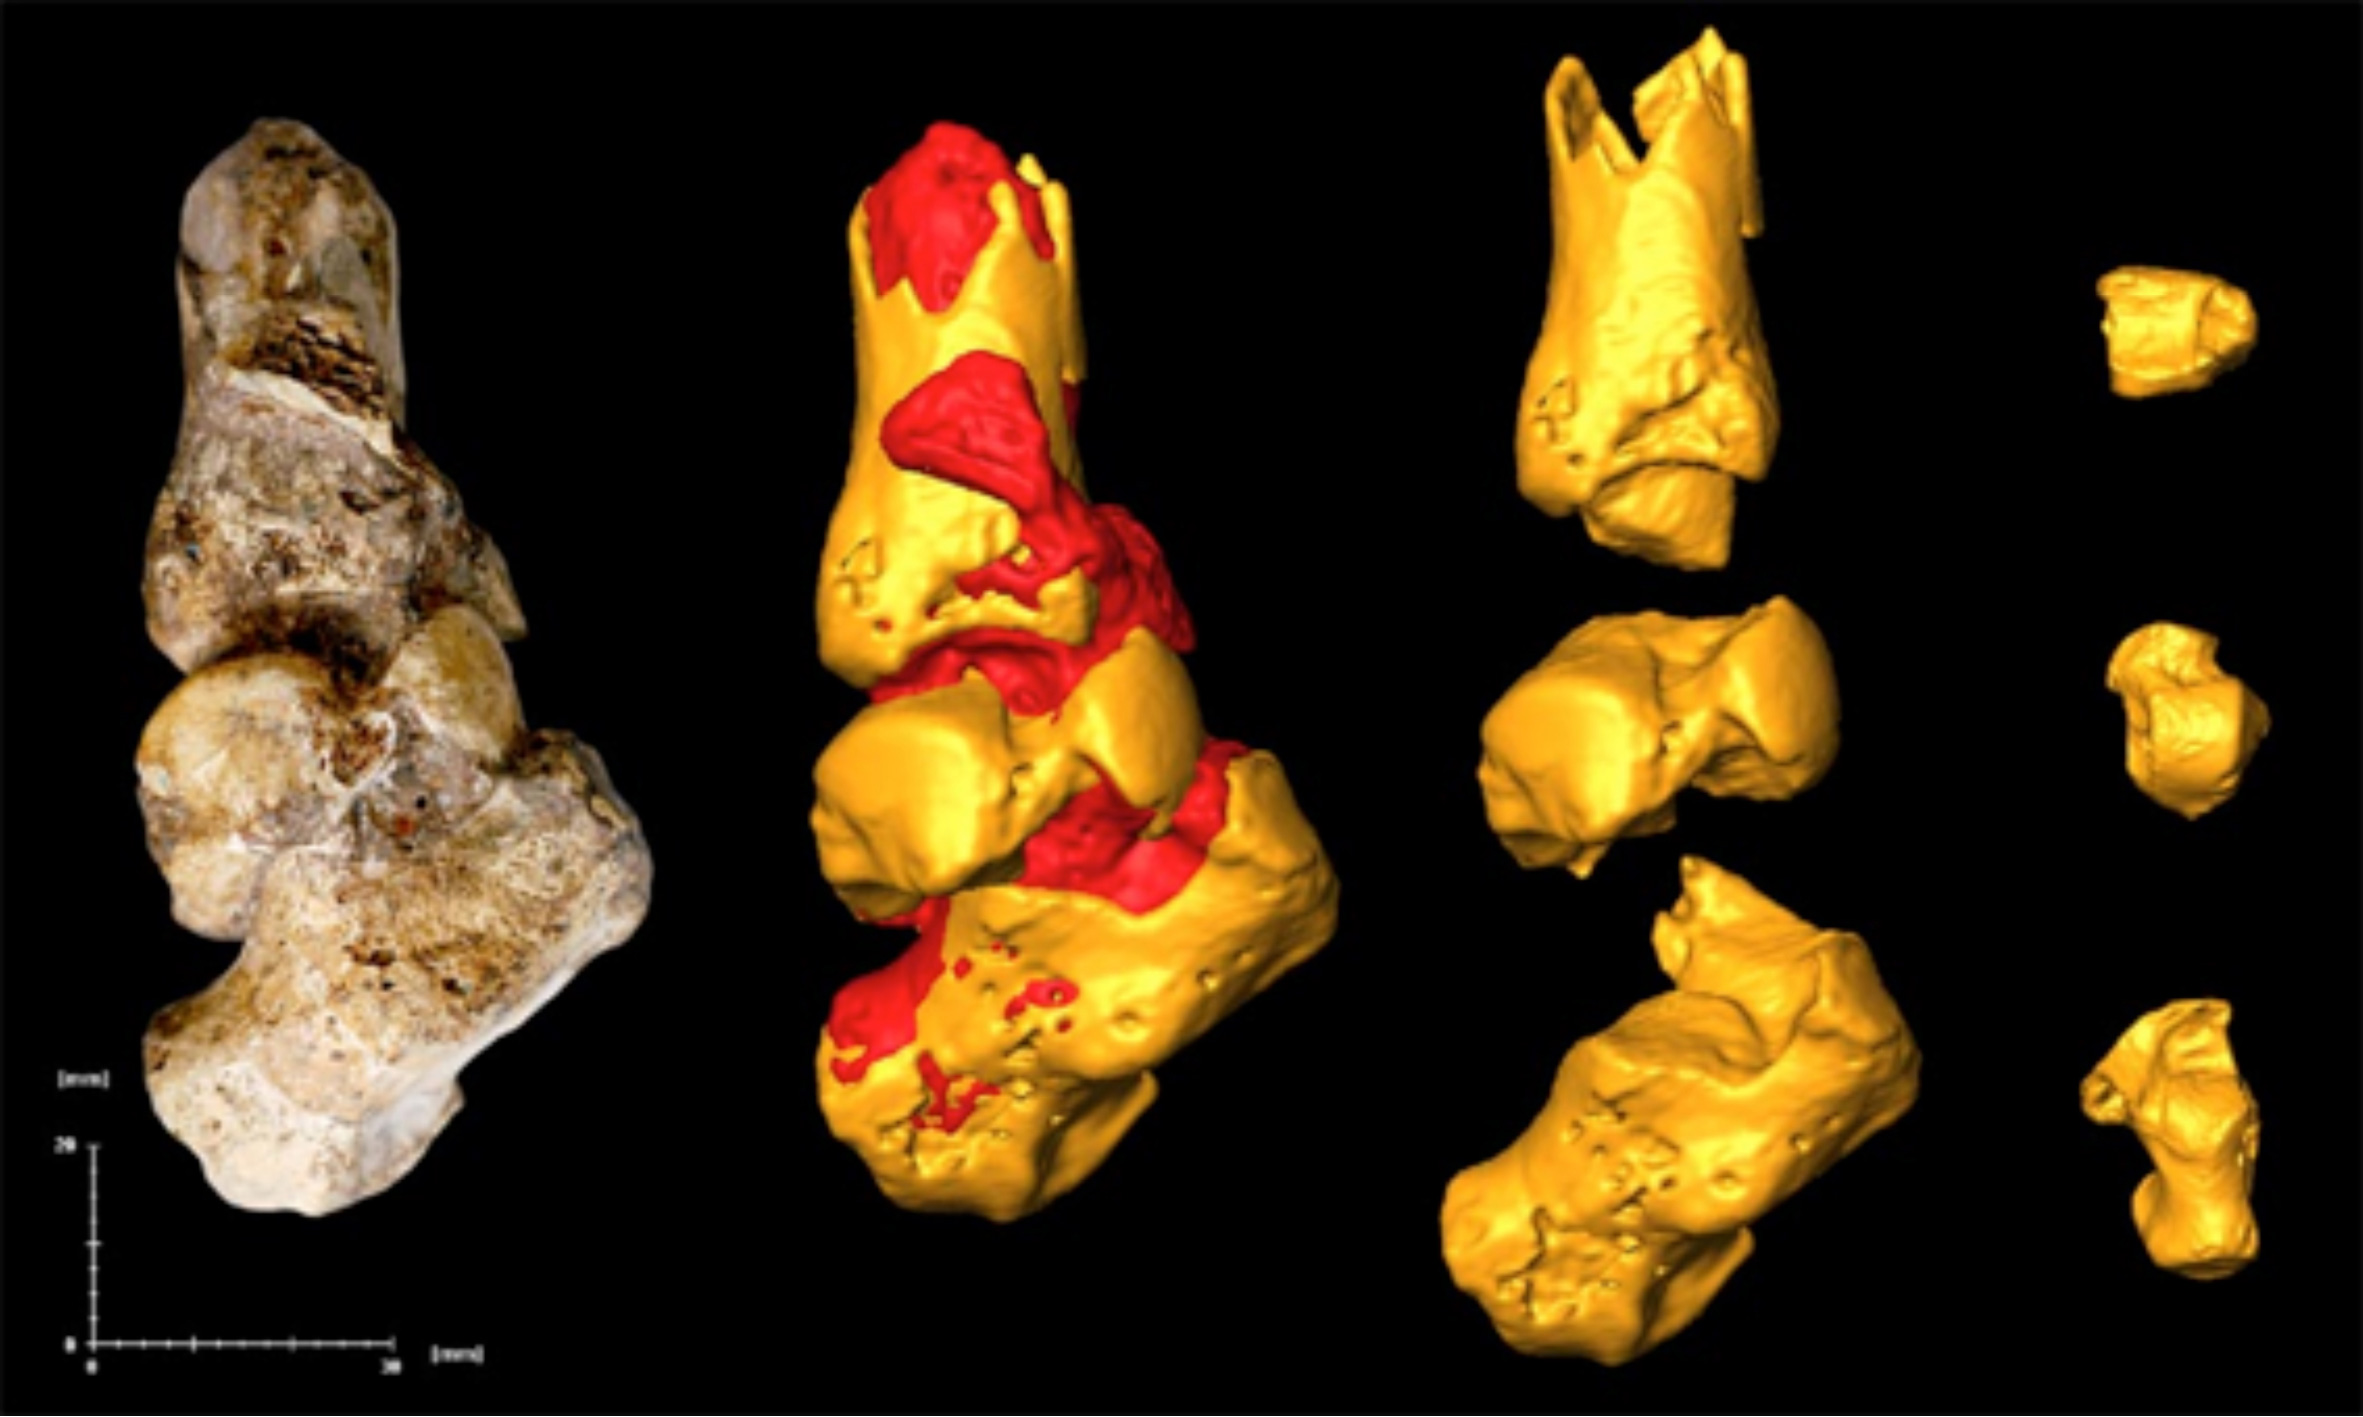

MH1 개체의 여섯 번째 흉추 오른쪽 판에서는 침투성 뼈 종양이 발견되었는데, 이는 아마도 양성 골성 골종으로 추정된다. 이 병변은 6.7mm 깊이로 뼈에 침투해 있었고 너비는 5.9mm였으며, 사망 당시에도 활성 상태였던 것으로 보인다. 종양이 척수관을 관통하지는 않아서 신경학적 합병증을 유발하지는 않았을 것으로 보이며, 척추 측만증(척추의 비정상적인 굽음)의 증거도 없다. 하지만 이 종양은 어깨뼈와 등의 오른쪽 위쪽 사분면 움직임에 영향을 미쳐 급성 또는 만성 통증, 근육 장애 또는 근육 경련을 유발했을 수 있다. ''오스트랄로피테쿠스 세디바''가 나무를 오르는 능력이 필요했을 수 있다는 점을 고려하면, 승모근, 척추기립근, 능형근과 같은 근육들의 부착 지점 근처에 병변이 위치하여 정상적인 움직임 패턴을 제한했을 가능성이 있다. MH1은 인류 화석 기록상 암이 진단된 최초의 사례로, 기존에 가장 오래된 것으로 알려졌던 남아프리카 공화국 스와르트크란스에서 발견된 180만 년에서 160만 년 전의 골육종을 나타내는 SK 7923 중족골 조각보다 최소 20만 년 앞선다. 영장류에서 종양은 일반적으로 발병률이 낮기 때문에 인류 화석 기록에서도 드물게 발견되며, 초기 인류 역시 현대 영장류와 비슷한 발병률을 가졌을 가능성이 높다. 어린 개체였던 MH1에서 뼈 종양이 발견된 것은, 뼈 종양이 주로 젊은 개체에게 발생하는 일반적인 경향과 일치한다.[34]